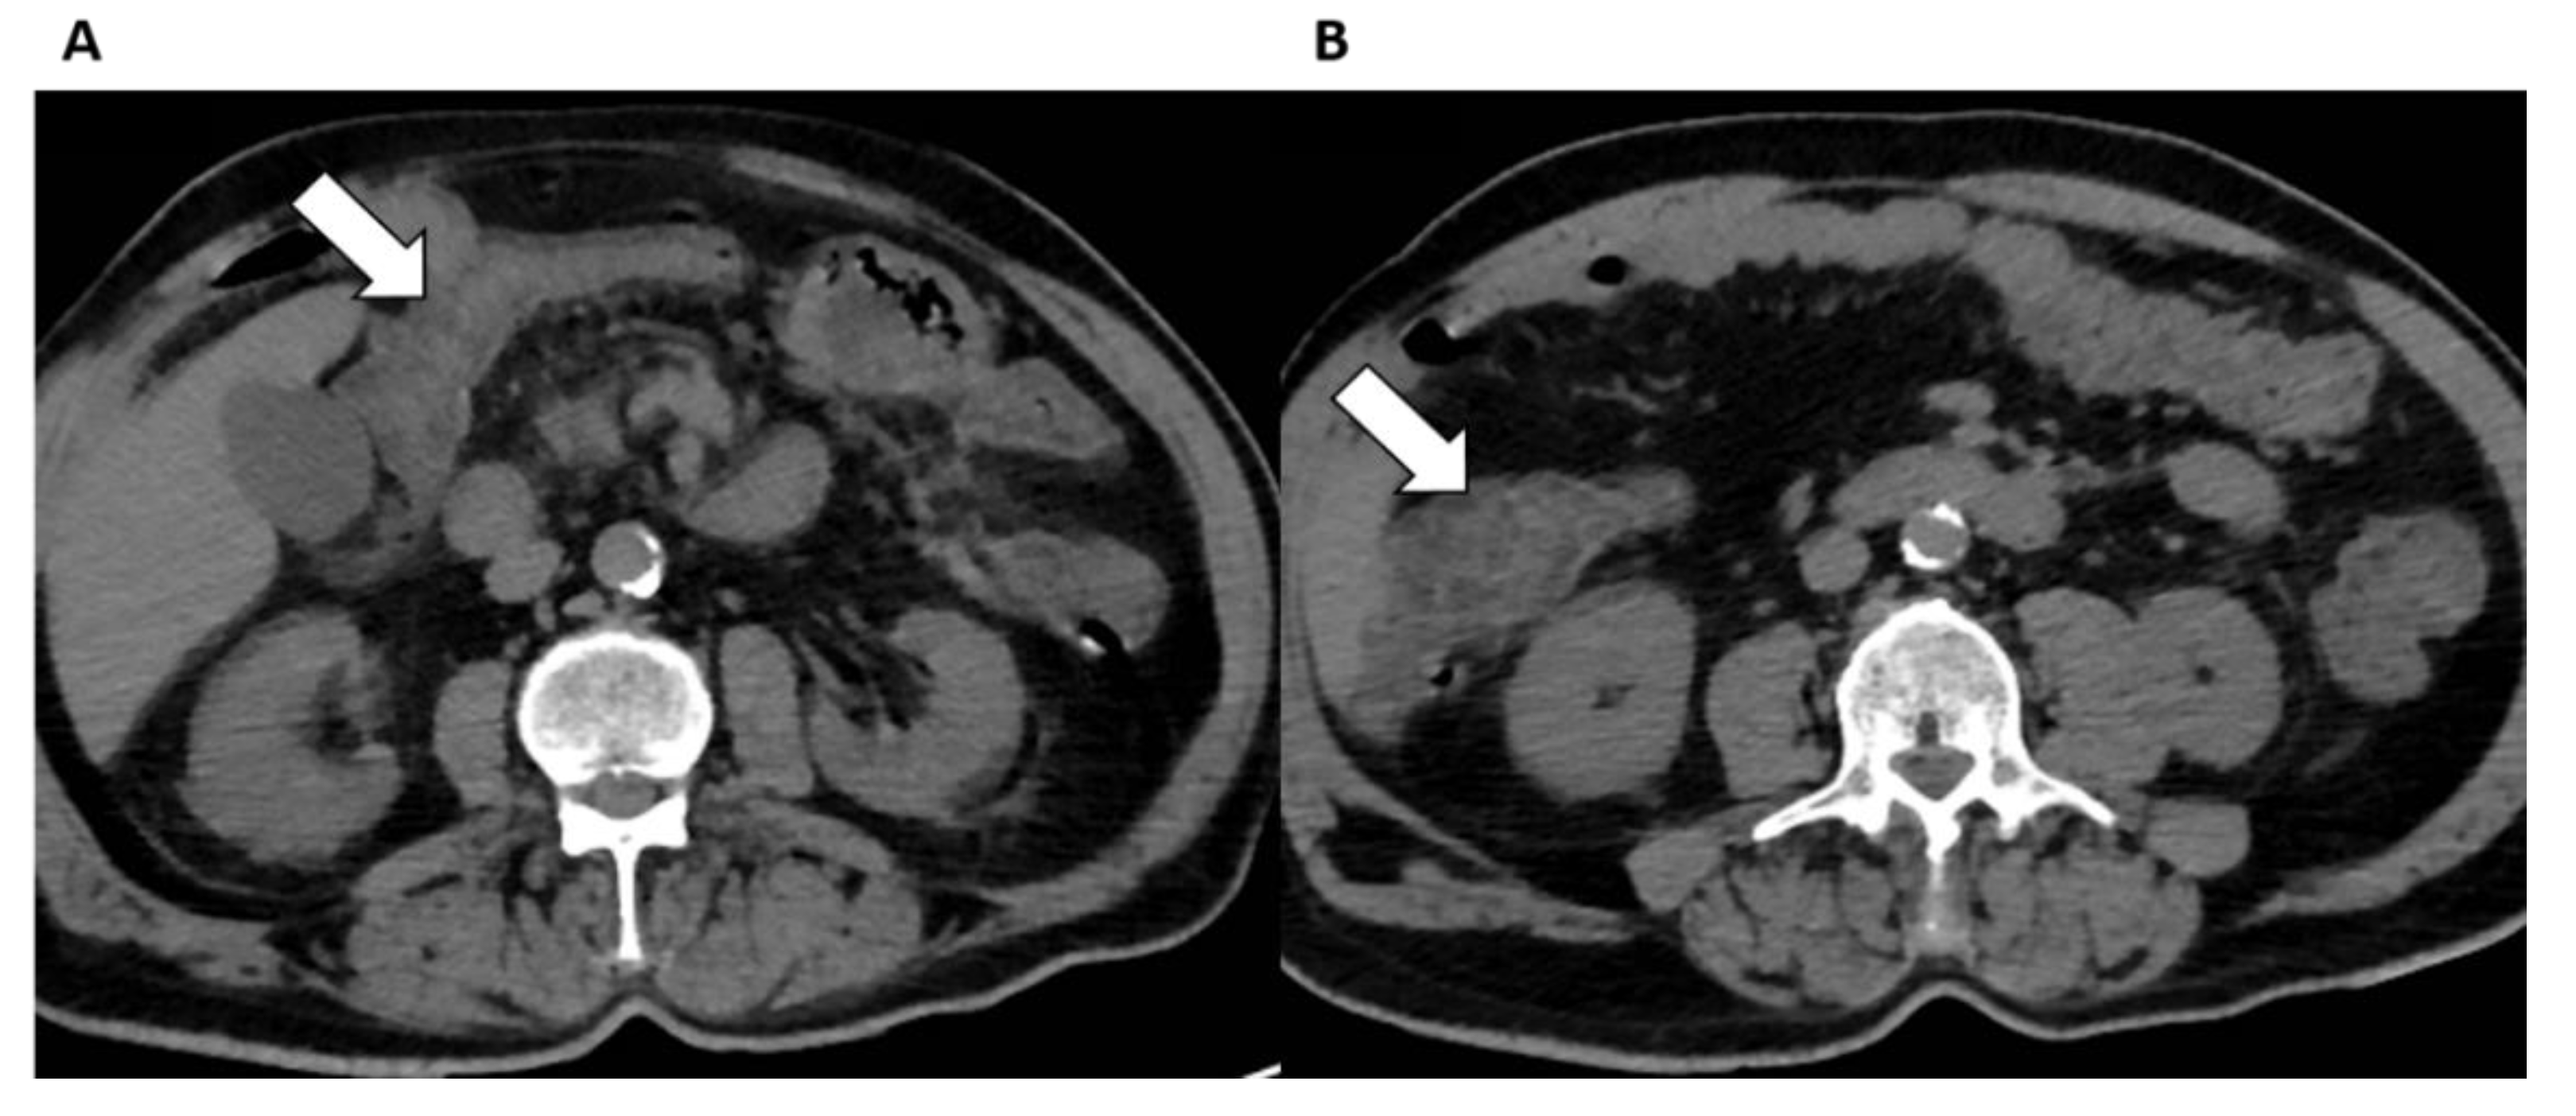

Abdominal CT scans performed in hospitalized patients with COVID-19 showed abnormalities in the bowel wall or fluid-filled colon in 18–31% and 43% of patients, respectively, with a significantly higher occurrence of these findings in ICU patients as compared to patients not in the ICU [78]. Bowel abnormalities (Figure 5) on CT include findings of inflammation, ischemia, obstruction, diverticulitis, and, even, perforation [74,78]. Macrovascular arterial or venous thrombosis is identified in almost half of COVID-19 patients with bowel ischemia [91]. Interestingly, abnormalities in the bowel seem to occur independently of severity of pulmonary involvement, other clinical and laboratory features [92].

Figure 5.

Intestinal findings in a COVID-19 patient admitted to the Emergency Department for abdominal pain. (A,B) Unenhanced axial abdominal CT images show bowel wall thickening in the transvers colon (arrows) with adjacent fat stranding consistent with intestinal involvement with ischemic lesions.